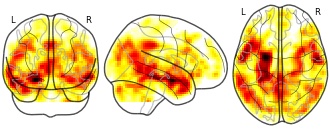

Comparisons of FC maps from different brain areas between sleep and d-PIS...

EmailClick to copy linkLink copied CiteYun Li; Shengpei Wang; Chuxiong Pan; Fushan Xue; Junfang Xian; Yaqi Huang; Xiaoyi Wang; Tianzuo Li; Huiguang He (2023). Comparisons of FC maps from different brain areas between sleep and d-PIS states. [Dataset]. http://doi.org/10.1371/journal.pone.0192358.t007xlsAvailable download formatsUnique identifierhttps://doi.org/10.1371/journal.pone.0192358.t007Dataset updatedJun 2, 2023Dataset provided byPLOS ONEAuthorsYun Li; Shengpei Wang; Chuxiong Pan; Fushan Xue; Junfang Xian; Yaqi Huang; Xiaoyi Wang; Tianzuo Li; Huiguang HeLicense

CiteYun Li; Shengpei Wang; Chuxiong Pan; Fushan Xue; Junfang Xian; Yaqi Huang; Xiaoyi Wang; Tianzuo Li; Huiguang He (2023). Comparisons of FC maps from different brain areas between sleep and d-PIS states. [Dataset]. http://doi.org/10.1371/journal.pone.0192358.t007xlsAvailable download formatsUnique identifierhttps://doi.org/10.1371/journal.pone.0192358.t007Dataset updatedJun 2, 2023Dataset provided byPLOS ONEAuthorsYun Li; Shengpei Wang; Chuxiong Pan; Fushan Xue; Junfang Xian; Yaqi Huang; Xiaoyi Wang; Tianzuo Li; Huiguang HeLicenseAttribution 4.0 (CC BY 4.0)https://creativecommons.org/licenses/by/4.0/

License information was derived automaticallyDescriptionComparisons of FC maps from different brain areas between sleep and d-PIS states.

Raw data of based-voxel functional connectivity in terms of ROIs.

EmailClick to copy linkLink copied CiteYun Li; Shengpei Wang; Chuxiong Pan; Fushan Xue; Junfang Xian; Yaqi Huang; Xiaoyi Wang; Tianzuo Li; Huiguang He (2023). Raw data of based-voxel functional connectivity in terms of ROIs. [Dataset]. http://doi.org/10.1371/journal.pone.0192358.s001zipAvailable download formatsUnique identifierhttps://doi.org/10.1371/journal.pone.0192358.s001Dataset updatedJun 4, 2023AuthorsYun Li; Shengpei Wang; Chuxiong Pan; Fushan Xue; Junfang Xian; Yaqi Huang; Xiaoyi Wang; Tianzuo Li; Huiguang HeLicense

CiteYun Li; Shengpei Wang; Chuxiong Pan; Fushan Xue; Junfang Xian; Yaqi Huang; Xiaoyi Wang; Tianzuo Li; Huiguang He (2023). Raw data of based-voxel functional connectivity in terms of ROIs. [Dataset]. http://doi.org/10.1371/journal.pone.0192358.s001zipAvailable download formatsUnique identifierhttps://doi.org/10.1371/journal.pone.0192358.s001Dataset updatedJun 4, 2023AuthorsYun Li; Shengpei Wang; Chuxiong Pan; Fushan Xue; Junfang Xian; Yaqi Huang; Xiaoyi Wang; Tianzuo Li; Huiguang HeLicenseAttribution 4.0 (CC BY 4.0)https://creativecommons.org/licenses/by/4.0/

License information was derived automaticallyDescriptionThe zip file can be unzipped to a set of MATALB *.mat files, which contain based-voxel functional connectivity data and relevant information. The whole data set can be divided into two groups, i.e., sleep group and anesthesia group. The sleep group data includes two states (sleeping and waking), while the anesthesia group data includes three states (waking, mild-PIS and deep-PIS). (ZIP)